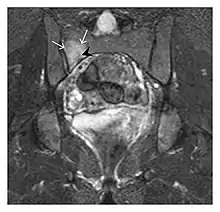

Proximal femoral fractures usually occur in osteoporotic patients, and their signs include subtle neck angulation, trabecular angulation, and subcapital impaction line. A frog-leg lateral view may be helpful if the greater trochanter is short enough. However, positioning can be difficult because of hip pain. In patients with strong suspicion of proximal femoral fracture and negative radiographs, MRI limited to coronal T1 W images and scintigraphy can be highly valuable (Figures 13 and 14). Such an option, with limited examination time, is cost-effective and allows reliable exclusion or confirmation of the diagnosis, preventing an unnecessary stay at the hospital or delayed treatment. Moreover, MRI helps to detect soft tissue abnormalities which are more frequently seen in femoral, acetabular, and pubic injuries than sacral lesions. Concomitant fractures are also frequently seen in typical pelvic sites.[1]

a

b

Figure 13: Partial osseous avulsion of the gluteal muscles at the greater trochanter in a 59-year-old man who presented with the right hip pain without a history of trauma. Lauenstein view and anteroposterior and radiographs (not shown) did not show an obvious fracture line or disruption of bony contours in the acetabulum or the right femoral neck. (a) Coronal T1-weighted MRI displays an incomplete fracture line extending partially from the greater trochanter (arrow). (b) Coronal short tau inversion recovery MRI shows heterogeneous hyperintensity in the same region (arrow) as well as hyperintensity within the gluteus medius and minimus muscles (arrowheads) consistent with tissue edema and hematoma.[1]